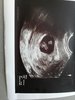

Ja już po wizycie... Wszystko ok 7 tydzień 1dzien, ciąża pojedyncza termin porodu 5 kwietnia. Usg miałam robione. Następna wizyta 9 wrzesnia. I oczywiście zlecone badania :D

Załączniki

• 15662031279996566727309453757220.jpg

15662031279996566727309453757220.jpg

2,5 MB · Wyświetleń: 124